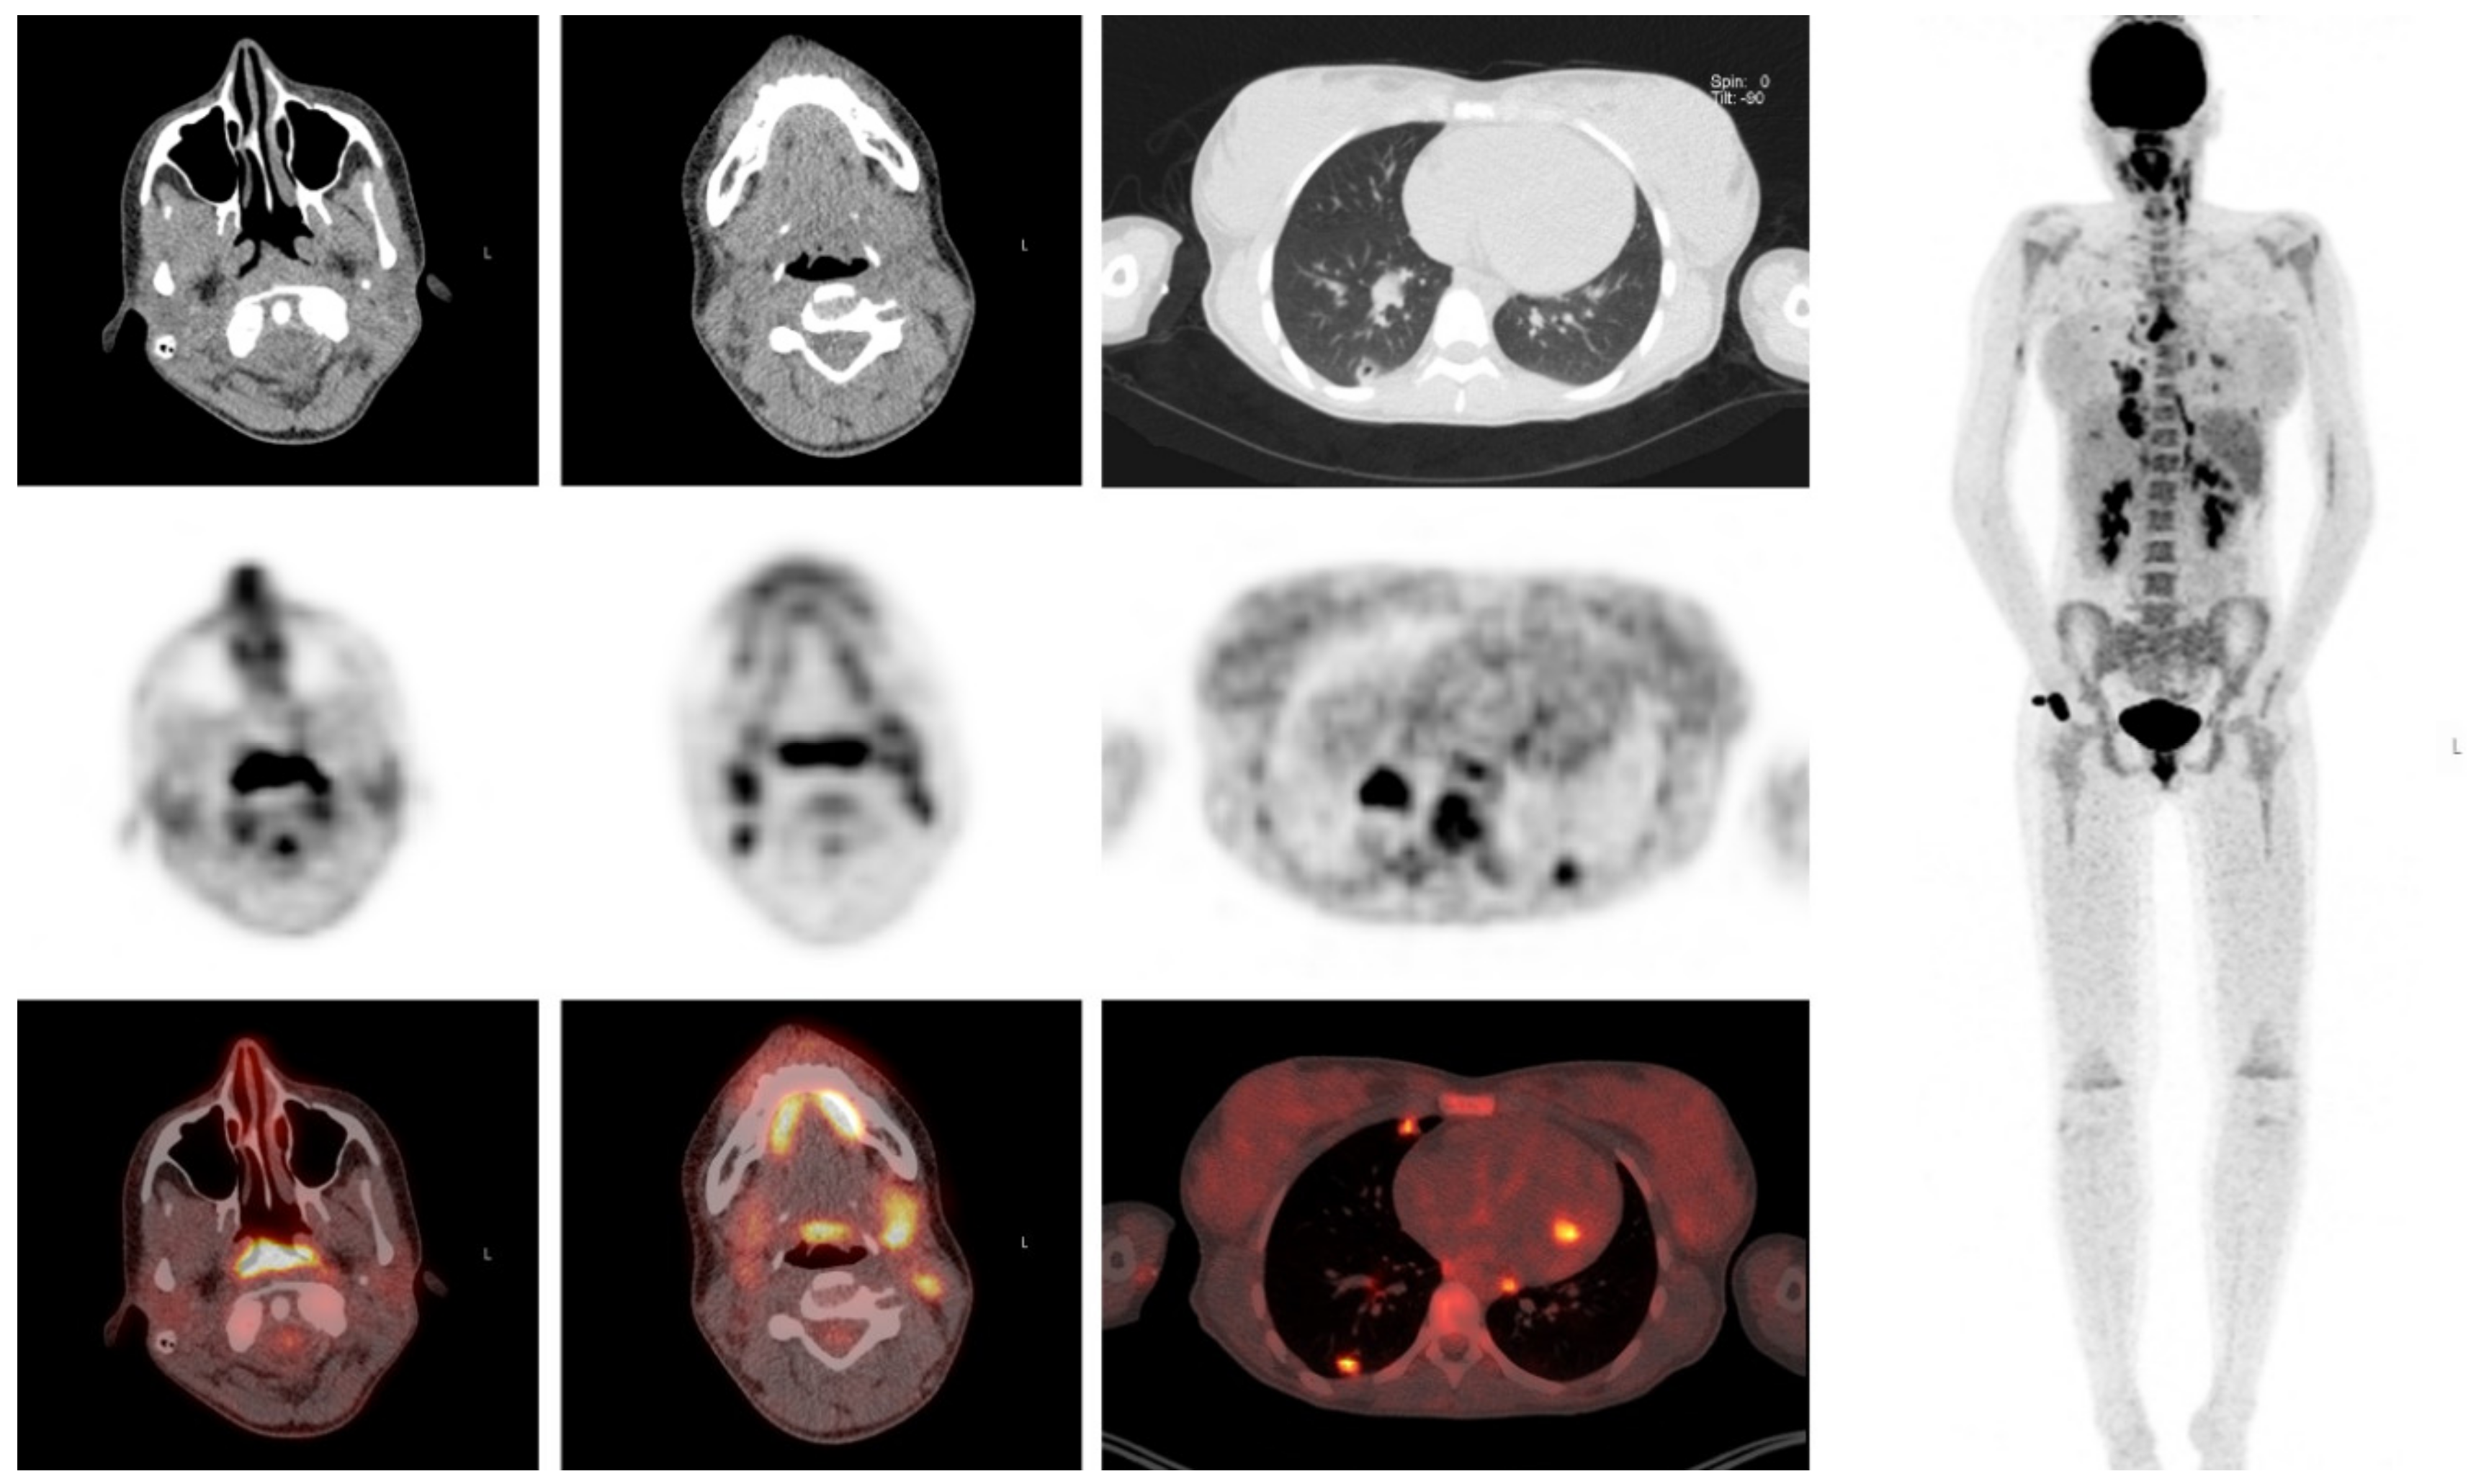

That is protocol whether or not they light up on a PET or not. The PET scan cant determine if its cancer or not it can show suspicion for. Axial CT image a revealed lymph node enlargement on 2R arrow.

From the lower margin of the cricoid to the clavicles and the upper border of the manubrium. PET coronal image b show multiple mediastinal lymph nodes high FDG uptake arrow. I dont have an answer for you as this is all new for me as well and today when I met with the radiation oncologist I was told that I needed a PET scan before treatment can begin due tp enlarged lymph nodes from my CT scan.

Lymph Nodes PET scan biopsy - Lung cancer - Inspire. The PET scan on the right lights up the structures that contain cancer thus helping prove that the cancer has already spread to these lymph nodes and changing the patients stage from stage I to stage III and eliminating surgery as a good treatment option. 1 days ago Sep 14 2019 I had no lymph nodes light up on my PET scan either.